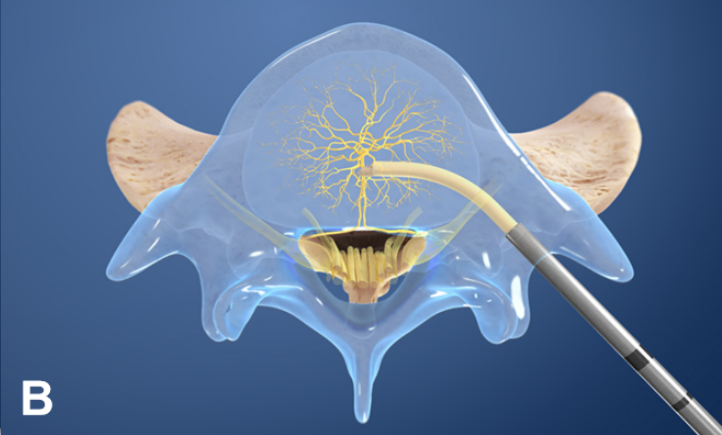

②椎体内椎基神经射频消融术

值得关注的是,系列前瞻性多中心随机对照研究和前瞻性观察研究证实椎体内椎基神经射频消融术可有效缓解疼痛性 Ⅰ 型或 Ⅱ 型 Modic 改变患者的腰痛症状,减少阿片类药物的用量,且疗效优于保守治疗。

国际脊柱外科手术学会指南也推荐采用椎体内椎基神经射频消融术治疗 Ⅰ 型或 Ⅱ 型 Modic 改变引起的慢性腰痛。

2021 年,Conger 等进行系统综述发现有中等质量的证据表明,在根据存在 Ⅰ 型或 Ⅱ 型 Modic 改变选择慢性腰痛患者时,椎体内椎基神经射频消融术可有效改善慢性腰痛患者的疼痛和功能障碍。这可能与灭活了椎体内的椎基神经, 阻断了神经传导通路有关。